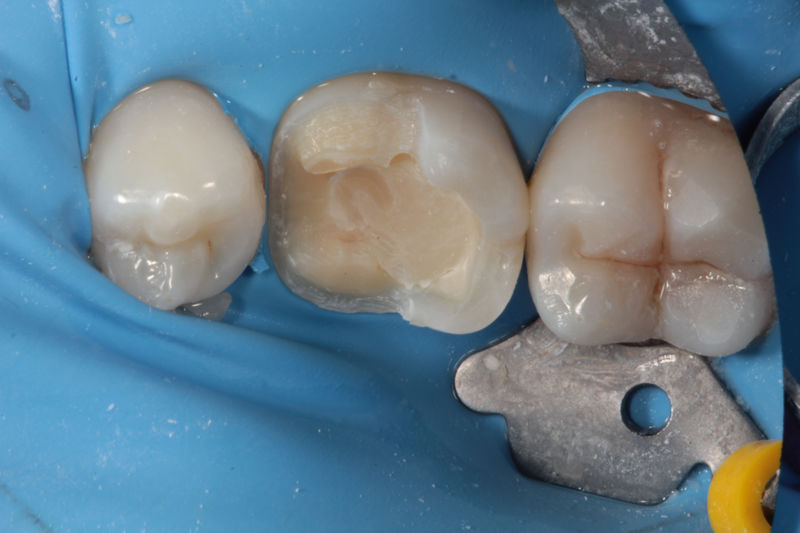

Restauraciones fabricadas en el laboratorio con materiales estéticos, los cuales cubren de manera parcial dientes posteriores. Se utilizan primariamente para restaurar dientes con caries, fracturas y/o defectos amplios. Para poder enviar el caso al laboratorio se toman impresiones utilizando materiales de impresión o técnicas modernas digitales.

Restauraciones fabricadas en el laboratorio con materiales estéticos, los cuales cubren de manera total dientes anteriores y posteriores. Se utilizan primariamente para restaurar dientes con caries, fracturas y/o defectos amplios, así como soportes de puentes. Para poder enviar el caso al laboratorio se toman impresiones utilizando materiales de impresión o técnicas modernas digitales.